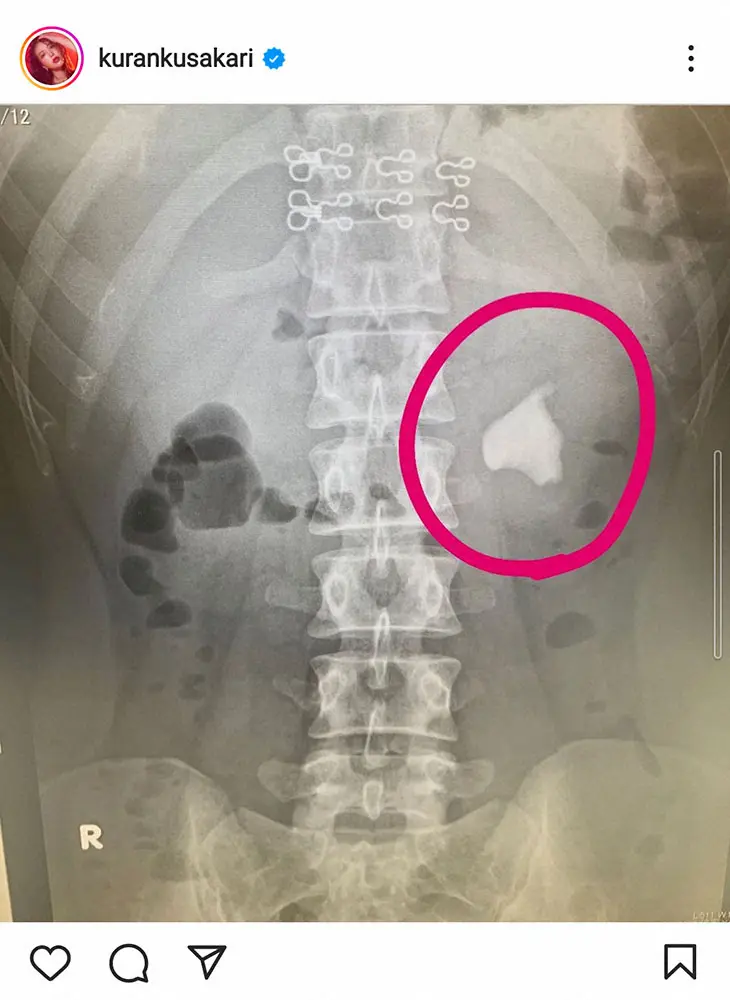

紅蘭公式インスタグラム(kurankusakari)から 紅蘭 膀胱炎が原因、3センチの巨大結石で手術…「なめていました。まず病… ギャラリーで見る この記事のフォト 2022年08月29日の画像一覧 もっと見る 2022年08月29日の画像をもっと見る